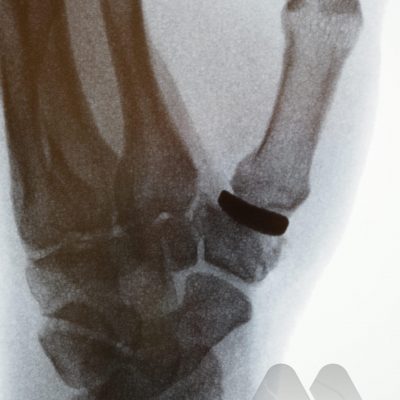

Common symptoms cause pain, and stiffness in the small joints of the hand. The knuckles can become swollen or show bumps and bony nodules called Heberden’s or Bouchard’s nodes in the fingers. Base of thumb arthritis can sometimes lead to the thumb being drawn into the palm and loss of a wide hand span. People often complain of difficulty opening jars and taps. X-Rays are often the most simple and effective way of showing arthritis.

This is the technique of fusing the joint in a position of best function that is appropriate to each individual patient. This is a very durable and reliable way of relieving pain and correcting severe deformity although it does prevent any movement of the affected joint from the fused position. It has been a technique employed since the early 1900’s with good long term results. It is particularly useful in younger patients with a requirement for heavy manual activity and commonly used to treat arthritis in the smaller joints of the fingers such as the DIP joints but can be performed in almost any joint. Risks of surgery include a failure to fuse the joint causing ongoing pain, risk of implant breakage or irritation to surrounding tissues, injury to surrounding structures including skin, nerves, blood vessels and cells that produce the nail and can also be complicated by infection.